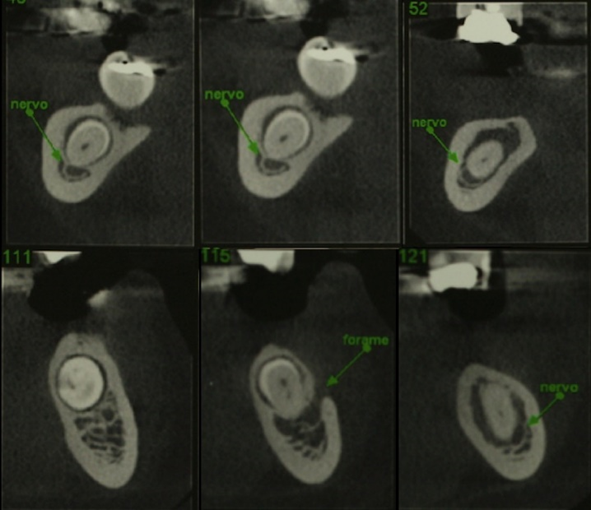

Case 2: A 42-year-old patient sought rehabilitation of the bilateral posterior mandibular region. In the imaging exams, impacted premolars were observed on both sides (figure 4). In the detailed tomography exams, it was observed that despite the close relationship between the inferior alveolar nerve and the impacted teeth, in both cases the crown presented a safe distance about the nerve (figure 5).

Figure 5: cone beam computed tomography showing an impacted premolars in an edentulous area (third and fourth quadrant).

Figure 6: cone beam computed tomography showing proximity of the inferior alveolar nerve to the crowns of the impacted premolars.